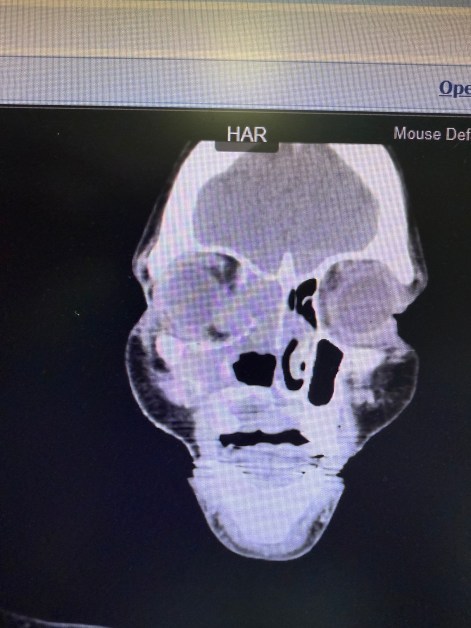

Giving Hope Through Jaw Reconstruction: Treating Ameloblastoma in Kenya

Ameloblastomas are benign but locally aggressive tumors that most often arise in the mandible (lower jaw). While they grow slowly, patients in Kenya frequently present with very large masses by the time they come for treatment — far larger than any I encountered during my surgical training in the United States. Once these tumors reach…